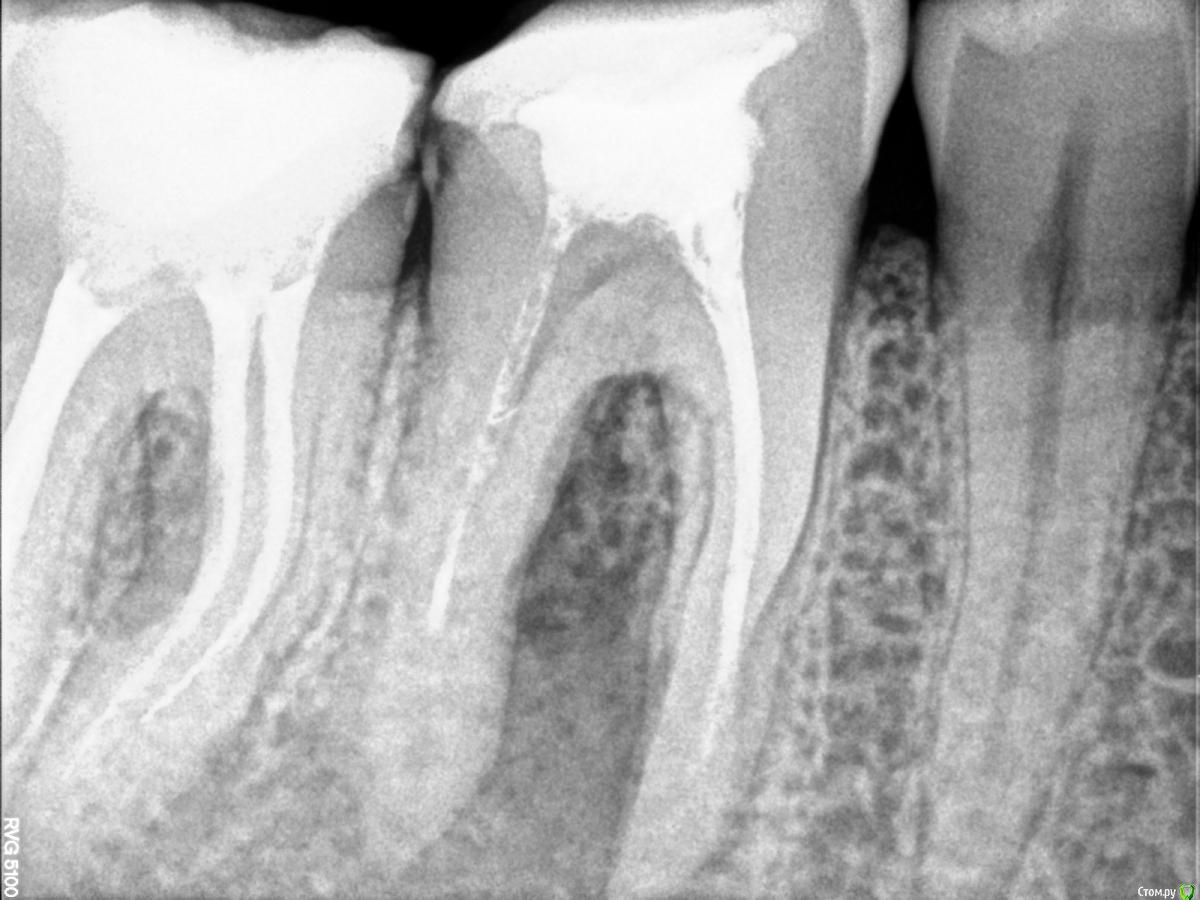

Bibika2020 Опубликовано 31 мая, 2020 Поделиться Опубликовано 31 мая, 2020 Всем добрый день. Предыстория:В 2018 году на зубе 46 откололся кусочек сзади и зуб начал сильно болеть. Зуб до этого был уже депульпирован лет 5-10 назад (уже не помню) и стоял со световой пломбой. В 2018 г. провели восстановление коронковой части зуба пломбой, в каналы не лазили.В 2019 году в районе этого зуба появился свищ, но зуб никак не беспокоил. Текущая ситуация:Весной 2020 года зуб начал реагировать на холодное и горячее и надкусывание средней степенью боли.Первое посещение врачаОбратился к врачу в марте (снимок 1 и 2). Доктор сказал, что можно попробовать перелечить каналы и сохранить зуб. Из трёх каналов один был не запломбирован, в двух других была гуттаперча. Доктор провела механическую и медикаментозную обработку двух каналов: незапломбированного и одного с гуттаперчей и заложила кальцийсодержащую пасту, поставила временную пломбу, выписала антибиотик 5 дней.Облегчение почувствовалось сразу. Через неделю свищ прошёл. Ещё через неделю опять появился. Второе посещение врачаКак раз подходило время очередного приёма, но доктор уже был другой в том же месте.Снимки 3 и 4. Доктор провела механическую и медикаментозную обработку двух каналов и заложила кальцийсодержащую пасту. Сказала, что временная пломба была сильно не герметична поэтому микробы попадали в зуб. Положила фум ленту и сделала световую пломбу 10 апреля. Свищ опять на какое-то время пропал и снова появился через пару недель. Третье посещение врачаНа следующем приёме доктор сделал снимок с гуттаперчей вставленной внутрь свища, на снимке гуттаперча дошла до низа левого канала, как раз того, который изначально не было запломбирован N лет назад (снимка, к сожалению, нет). Дальше подключился хирург и сказал, что такой зуб нужно удалять, т.к. гранулирующий периодонтит (если я правильно запомнил). Сейчас прошло почти 2 месяца есть неприятные ощущения от зуба и свищ то появляется, то пропадает. ВопросЗуб жалко удалять, на мой взгляд, он нормальный.Хотелось бы услышать мнение врачей, есть шанс сохранить зуб и что делать? Ссылка на комментарий

Kolchanov Опубликовано 1 июня, 2020 Поделиться Опубликовано 1 июня, 2020 Периодонтит. Причем еще соседний зуб может поддерживать процесс. Да и тот, которым сейчас занимаются.... Перелечивать надо всё, все каналы. Еще ощущение есть, глядя га снимок, что полость зуба так и не была раскрыта. Но это, конечно, надо "вживую" смотреть.По снимку зуб выглядит вполне достойным того, чтобы пробовать. А, если удалять, то еще и 7ку сразу, а то мало ли... Ссылка на комментарий

Bibika2020 Опубликовано 1 июня, 2020 Автор Поделиться Опубликовано 1 июня, 2020 (изменено) Вот ещё на снимке смущает (обвёл красным):1. на правых корнях 7го зуба волнистые линии это не остатки инструмента?2. непонятная загагулина на проблемном канале 6го зуба. что это может быть ? А что означает раскрытие полости зуба? Это его рассверливание, чтобы легче было к каналу доступ осуществить? Изменено 1 июня, 2020 пользователем Bibika2020 Ссылка на комментарий

dok1 Опубликовано 1 июня, 2020 Поделиться Опубликовано 1 июня, 2020 Щестёрка с булавоообразным утолщением корня. Пошла резорбция апекса. Плюс резорбция в просвете каналов. Я в шестой неверю . По этому бы рекомендовал удалить. Седьмой, если удастся извлечь инструмент, можно вылечить Ссылка на комментарий